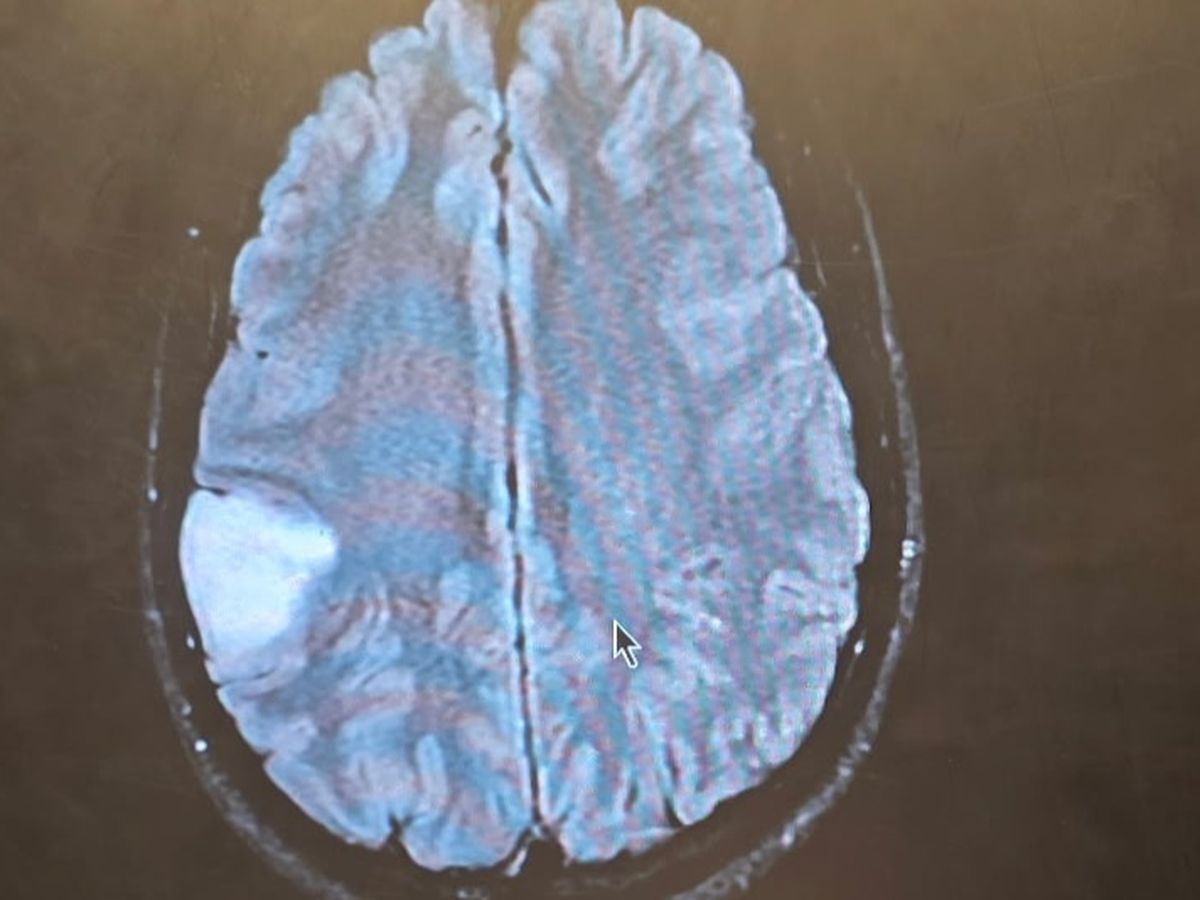

My 32-year-old son Tanner recently experienced a terrifying health crisis. He suddenly lost feeling on the left side of his body, and his wife rushed him to the nearest hospital. After being transferred by ambulance to St. Cloud, doctors performed an MRI and discovered that Tanner had not suffered a stroke, but a seizure. The MRI revealed a mass on his brain the size of a golf ball, pressing on the area that controls his motor skills.